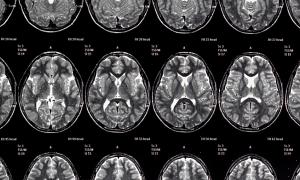

מה קורה למוח שלך לפני שאתה מת?

אחת התעלומות הגדולות ביותר של האנושות היא מה קורה למוח לפני שאתה מת. מדענים ברחבי העולם חיפשו את התשובה לשאלה הזו, אבל אף אחד לא הצליח למצוא תשובה ברורה.

המוח הוא האיבר בגוף הפגיע ביותר להיפוקסיה ואיסכמיה. היפוקסיה היא כאשר איבר אינו מקבל מספיק חמצן בדם. איסכמיה, לעומת זאת, היא השעיה או הפחתה של מחזור הדם לאזור מסוים. מחסור בחמצן גורם לנזק תאי.

הפרעה בזרימת הדם למוח גורמת לנזק בלתי הפיך לנוירונים הללו תוך פחות מעשר דקות. זה יכול לקרות לאחר דום לב-נשימה, למשל.

זה מפעיל דפוס של הפצה שבו הדפולריזציה המורחבת יכולה לפלוש לרקמה. נראה שדפולריזציה זו ניכרת רק עם ניטור עצבי המשתמש בהדמיה עצבית. חוקרים הצליחו להסיק שהמוח האנושי מגיב לאיסכמיה חמורה במוח עם דפוס פתולוגי קונקרטי. סוגים מסוימים של נוירונים מנסים למנוע מהמוח למות על ידי יצירת חוסר איזון חשמלי.

כאשר המוח מפסיק לקבל את הדם המחומצן, הנוירונים מנסים לאסוף את המשאבים שנותרו להם. דיכאון לא מפוזר מתרחש, ואחריו דה-פולריזציה המתפשטת, המכונה גם "צונאמי מוחי".

אז מה קורה למוח שלך לפני שאתה מת? לסיכום, התפשטות הדפולריזציה מסמנת את תחילתם של שינויים רעילים בתאים המובילים למוות. עם זאת, דה-פולריזציה לבדה אינה סימן למוות בטוח מכיוון שניתן להפוך אותה. יש עדיין הרבה מה לחקור בנושא זה, וזו הסיבה שיש צורך במחקרים נוספים.